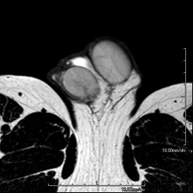

Prueba diagnóstica no invasiva que consiste en la obtención de imágenes de alta definición anatómica de la región escrotal mediante el empleo de un campo electromagnético y ondas de radio (con un emisor y un receptor). No utiliza radiación ionizante. En ocasiones se deberá emplear contraste paramagnético (Gadolinio) para completar el estudio. Se utiliza para el estudio detallado de los testículos, para identificar posibles tumores u otras patologías, además de poder visualizar alteraciones de las estructuras adyacentes. - RM Peneana